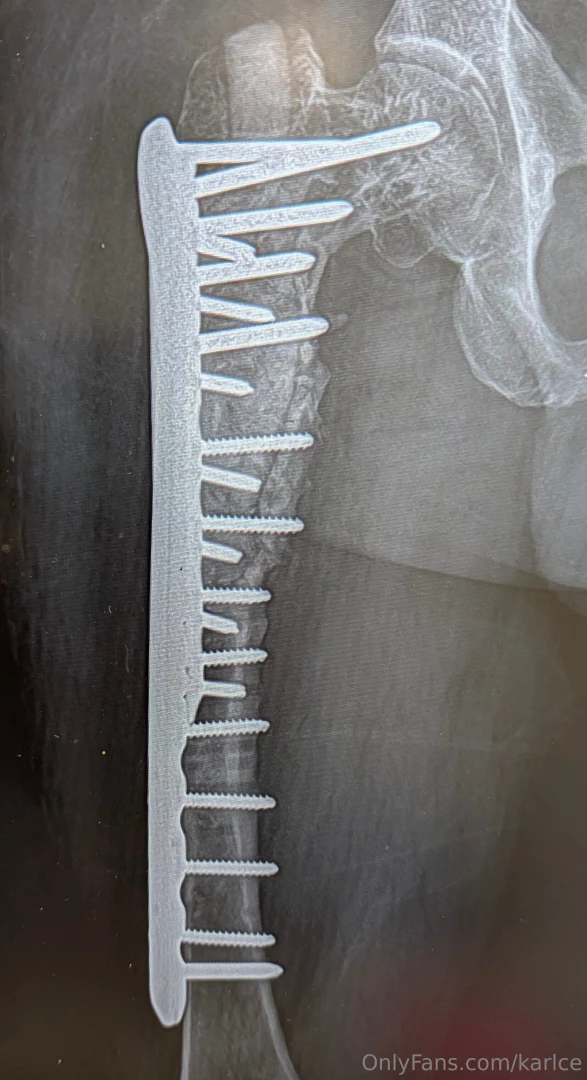

Latest set of hardware for those interested